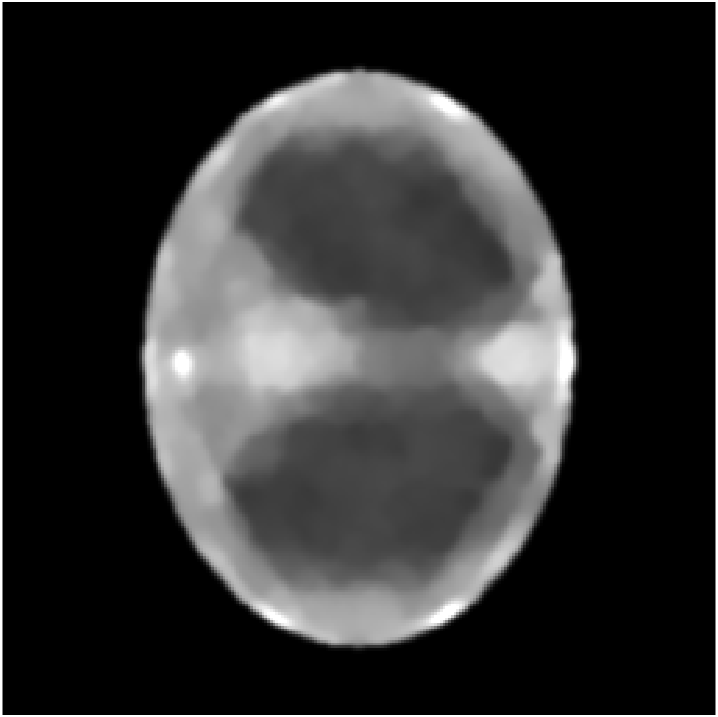

The method is tested for two synthetic phantoms; firstly, the thorax phantom already used in section 2. Figure 8 shows how the algorithm succeeds in decreasing the impact of the higher-order scattering. The ground truth is displayed in fig. 8(a). Expectably, the CT reconstruction (fig. 8(d)) is not accurate enough, but can be used as a prior to estimate the nonlinear weight function . Using , the CST reconstruction is computed. For comparison, we give both the solution of eq. 25 (without ) and eq. 26 (with ). As in section 2, eq. 25 cannot yield a useful reconstruction. The minimizer when is the Kullback-Leibler divergence (13) and is very noisy (fig. 8(b)) and using TV regularization, some noise can be filtered out, but only at the cost of losing small details of lower contrast (fig. 8(e)). As desired, applying to the data reduces the noise level, see fig. 8(c) and fig. 8(f) (with TV regularization). After applying , we use the norm as data fidelity measure. Densities and contrasts are accurately recovered and previously vanished details can be correctly located.

Figure 9 shows the reconstructions in the case of an aluminium ring on a pixel image (one pixel corresponds to ). In fig. 10 the same results but with an iron ring are displayed. From a sparse-view CT step (16 source positions and 32 detectors), the rough contours of the object are reconstructed well if we apply large parameters, but there are artifacts and the crack is clearly invisible, see figs. 9(d) and 10(d). Also, the iron already creates greater artifacts so that larger parameters have to be chosen to obtain a smooth image. Taking as the forward model, the different effects of aluminium and iron on the data become clearer: The higher attenuation of iron leads to more noise and circular artifacts aligned with the source positions, fig. 10(b) is worse than the aluminium case in fig. 9(b). Using TV-regularization, the crack is vaguely visible in the aluminium phantom, but not in the iron version (figs. 9(e) and 10(e)). Including the derivative greatly improves the quality of both reconstructions (figs. 9(c), 9(f), 10(c) and 10(f)), although only the aluminium version with tuned TV parameter appears accurate enough to exactly determine the nature of the crack in the plastic.

Apart from the computation of a second weight matrix, the reconstructions are computed the same way as in the monochromatic case. We only give the solutions of eq. 26 for the thorax phantom (fig. 11) and the second phantom in the aluminium case (fig. 12). The results are of equally convincing quality as in the case of a monochromatic source. With prior from the initial sparse-view CT step, the forward model is sufficiently accurate to recover both phantoms with few artifacts from the data . Using a differentiation step, the impact of and possibly higher-order terms on the reconstruction are decreased due to their smoothness. TV regularization is used in order to take care of the remaining noise generated by the Poisson process.